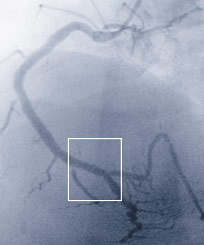

Verschluss an der rechten Herzkranzarterie

Mittels Angiographie werden die Herzkranzgefässe dargestellt. Im Bild sichtbar ist der Kontrastmittelstopp an der verschlossenen Stelle.

Dem Infarktereignis zugrunde liegt in aller Regel ein abrupter Verschluss eines Herzkranzgefässes durch ein Blutgerinnsel, das lokal an einer verengten Stelle entstanden ist (siehe Abb. 1 und 2). Früher wurde versucht, das Gefäss durch Auflösen des Thrombus wieder zu eröffnen. Hierfür wurden gerinnungshemmende Substanzen intravenös verabreicht. Die Auflösung gelang aber nur bei einem Teil der Patienten und es konnten teils bedrohliche Blutungskomplikationen auftreten.

Mittlerweile hat sich die direkte Wiedereröffnung einer verschlossenen Koronararterie mittels kathetertechnischer Ballondilatation und Stent-Implantation (PCI) als deutlich überlegene Behandlungsstrategie herausgestellt (siehe Abb. 3 und 4). Weltweit wird deshalb diese Behandlungsform wenn immer möglich als sofortige Erstbehandlung des akuten Herzinfark- tes angestrebt. Der Faktor Zeit spielt dabei eine ausschlaggebende Rolle.